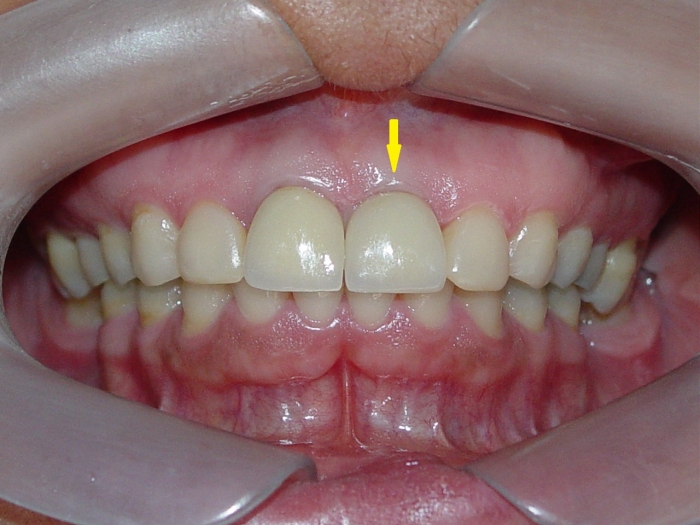

Prótese fixa em porcelana sobre implante Cone Morse